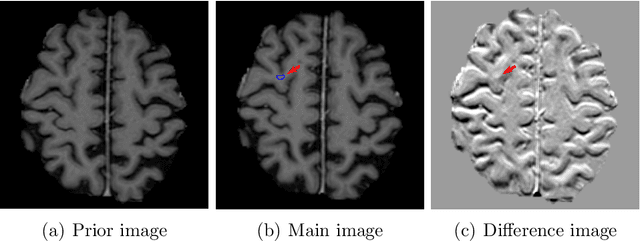

Abstract:Brain metastases occur frequently in patients with metastatic cancer. Early and accurate detection of brain metastases is very essential for treatment planning and prognosis in radiation therapy. To improve brain metastasis detection performance with deep learning, a custom detection loss called volume-level sensitivity-specificity (VSS) is proposed, which rates individual metastasis detection sensitivity and specificity in (sub-)volume levels. As sensitivity and precision are always a trade-off in a metastasis level, either a high sensitivity or a high precision can be achieved by adjusting the weights in the VSS loss without decline in dice score coefficient for segmented metastases. To reduce metastasis-like structures being detected as false positive metastases, a temporal prior volume is proposed as an additional input of the neural network. Our proposed VSS loss improves the sensitivity of brain metastasis detection, increasing the sensitivity from 86.7% to 95.5%. Alternatively, it improves the precision from 68.8% to 97.8%. With the additional temporal prior volume, about 45% of the false positive metastases are reduced in the high sensitivity model and the precision reaches 99.6% for the high specificity model. The mean dice coefficient for all metastases is about 0.81. With the ensemble of the high sensitivity and high specificity models, on average only 1.5 false positive metastases per patient needs further check, while the majority of true positive metastases are confirmed. The ensemble learning is able to distinguish high confidence true positive metastases from metastases candidates that require special expert review or further follow-up, being particularly well-fit to the requirements of expert support in real clinical practice.